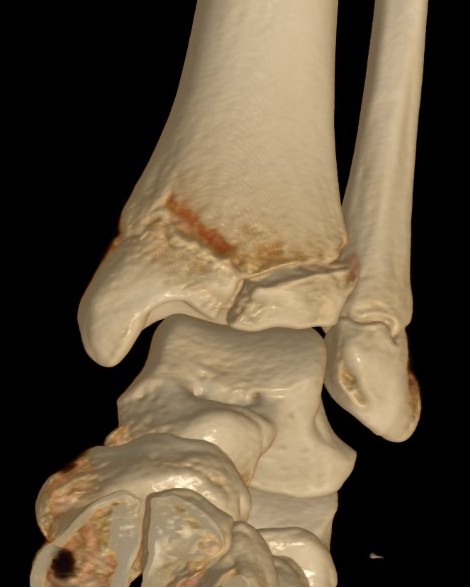

Triplanar Fracture

Definition

Fracture in coronal, sagittal and transverse planes

- crosses epiphysis

- passes through growth plate

- extends into metaphysis

Xray

AP xray: Salter-Harris type III / Tillaux

Lateral xray: Salter-Harris Type II

CT

Coronal images: Salter-Harris type III

Sagittal images: Salter-Harris type II

Axial images: 3 point star